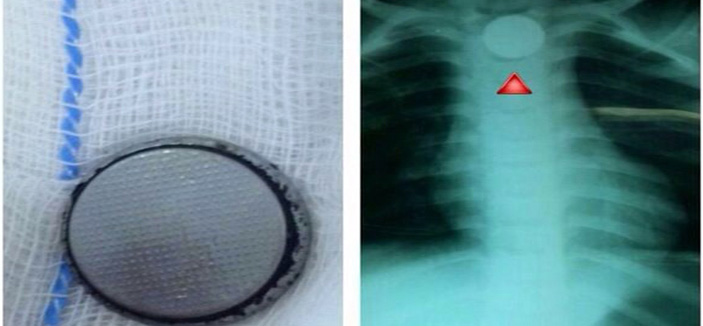

نجح فريق طبي بمستشفى خميس مشيط العام بقيادة استشاري جراحة الأنف والأذن والحنجرة والرأس والرقبة الدكتور أحمد العتودي، من استخراج بطارية صلبة من مريء طفلة تبلغ من العمر أربع سنوات.

حيث راجع ذوو الطفلة طوارئ المستشفى بعد ابتلاع الطفلة لجسم غريب اعتقدوا أنه عملة معدنية بعد معاينة المريضة وعمل الفحوصات اللازمة تبين وجود جسم غريب في المريء، حيث تم نقل المريضة على وجه السرعة إلى غرفة العمليات وتم عمل منظار تحت تأثير المخدر العام وتم استخراج بطارية صلبة من مريء الطفلة.